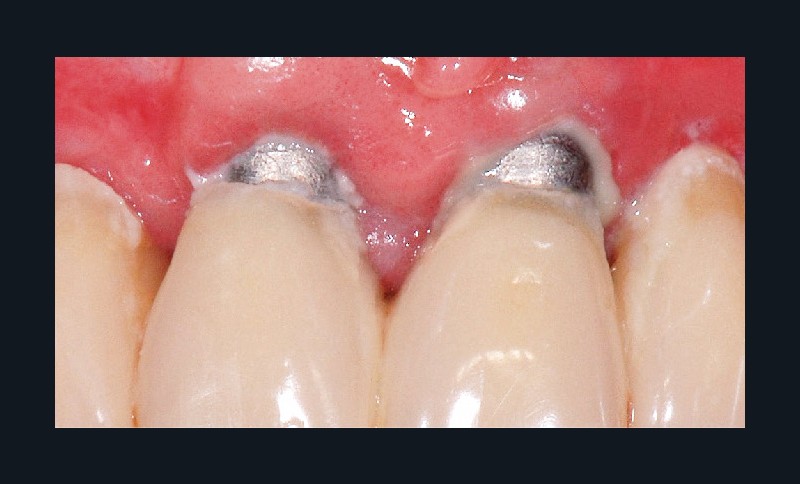

La plaque bactérienne (biofilm) pénètre et envahit les tissus muqueux autour des implants dentaires (fig. 3). S’installent une inflammation de la muqueuse péri-implantaire et la perte progressive et asynchrone du tissu osseux [4]. La péri-implantite survient au cours des premières années de mise en fonction de l’implant [4] et en l’absence de traitement, la maladie progresse (fig. 4) de manière non linéaire et rapide [4, 7].